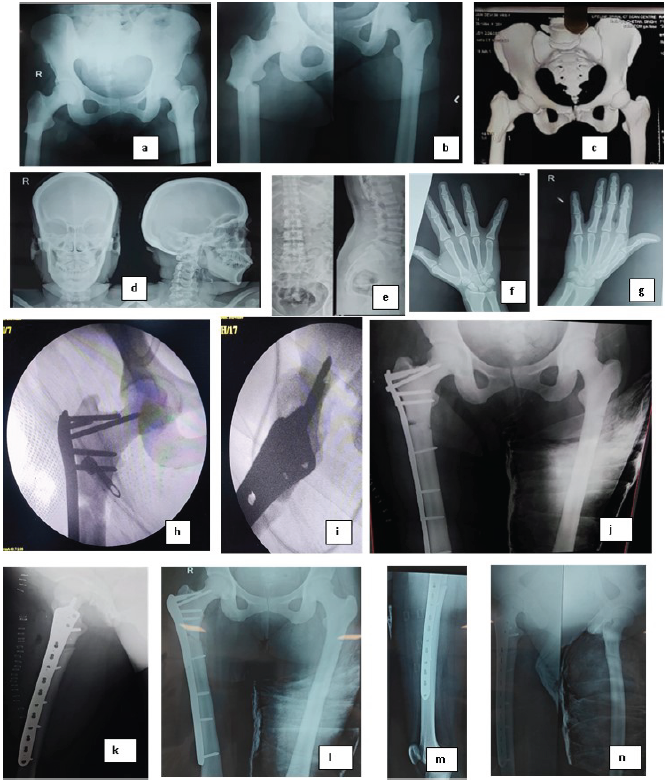

Bilateral hip, pelvic, and thigh xray confirmed subtrochanteric fractures. Complete fracture on the right side and unicortical fracture on the left side [Fig. 1]. X-rays of the skull, hands, and spine showed increased bone density, a characteristic feature of osteopetrosis. [Fig. 1]

Figure 1: Case I. (a and b) X-ray showing subtrochanteric fractures. The right femur demonstrates a complete fracture, while the left femur shows a unicortical fracture with Pelvic bones showing increased bone density characteristic of osteopetrosis, (c) 3D computed tomography of the hips and pelvis showing increased bone density and fracture sites. (d) X-ray skull showing thickened and dense skull bones, (e) X-ray spine showing bone within bone appearance, (f and g) X-ray hand showing increased bone density and loss of corticomedullary differentiation, (h) intraoperative fluorescent images of the fixation of fracture with plate, (i and j) postoperative X-ray of the fixation showing good alignment and fixation, (k-n) 2 months post-operative X-ray showing signs of union at both right and left side.

CT scan Provided a detailed view of the fractures and confirmed the diagnosis of osteopetrosis, showing abnormally dense bone structure in the pelvis, femurs, and other skeletal regions. [Fig. 1]. Complete Blood Count (CBC): Haemoglobin: 11.9 mg/dL, White blood cell count: 11,400 cells/mm³ (84.1% neutrophils, 11.3% lymphocytes), RBCs: 3.98 million cells/mm³, Platelet count: 1.66 lac cells/mm³, Acid phosphatase: 8.20 (elevated, often seen in osteopetrosis) [3], Erythrocyte sedimentation rate (ESR): 20 mm/hour, C-reactive protein (CRP): 1.79 mg/L, Parathyroid hormone (PTH): 53.36 pg/mL, Uric acid: 520 µmol/L, Prothrombin time (PT): 15.0 s, INR: 1.12, Liver function tests: SGOT 204 IU/L, SGPT 114 IU/L (mildly elevated)

The right-sided complete fracture was treated with open reduction and internal fixation (ORIF) using a femoral locking plate as there was no visible medullary canal on radiographs. The patient received spinal anesthesia and was positioned supine on a traction table. A standard lateral incision was made, and the fracture was reduced, with temporary fixation achieved using bone-holding forceps and K-wires. Fluoroscopic guidance was used to confirm reduction. [Fig. 1]

For definitive fixation, a 13-hole contralateral distal femur (DF) locking plate was selected. Due to the increased bone density characteristic of osteopetrosis, several modifications to standard surgical techniques were necessary. Drilling was performed using a low-speed, high-torque electric drill, with 3.0 mm pilot holes sequentially enlarged to 4.5 mm, using stainless steel bits under continuous saline cooling to prevent overheating of the dense bone. Despite the use of self-tapping screws, we employed a tap for better insertion due to the significantly increased cortical density. The duration of surgery was 2.5 hours, and blood loss was approximately 250 mL.

The procedure was prolonged as technical difficulties were encountered during drilling, with two instances of drill bit breakage. However, the surgery was completed successfully without complications.

Postoperative X-rays confirmed accurate placement of the internal fixation on the right femur, with good apposition and alignment of the fracture fragments [Fig. 1]. The patient’s recovery was uneventful, and she was discharged with instructions for follow-up and rehabilitation. Weight-bearing was started 3 months postoperatively. At the final follow-up at 1 year patient walks without support without any limp.